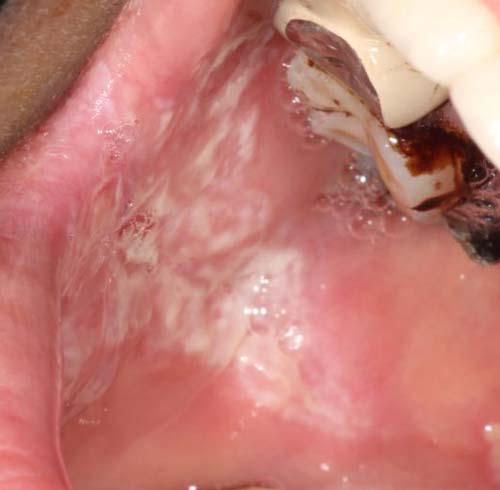

4、口腔白斑

和扁平苔藓一样,口腔白斑也是一种潜在恶性疾患,在吸烟人群中发病率高。好发于中老人男性。一般没有明显的症状,仅在局部有粗糙感,在伴溃疡时有疼痛不适。分为均质性和非均质性,非均质性的恶变率较高。

前方高能预警,请谨慎查看。

治疗方式:口腔白斑是口腔鳞状细胞癌的重要来源,1-3月定期复查,目前光动力治疗是一个不错的选择,友谊医院的门诊也可以进行光动力治疗。